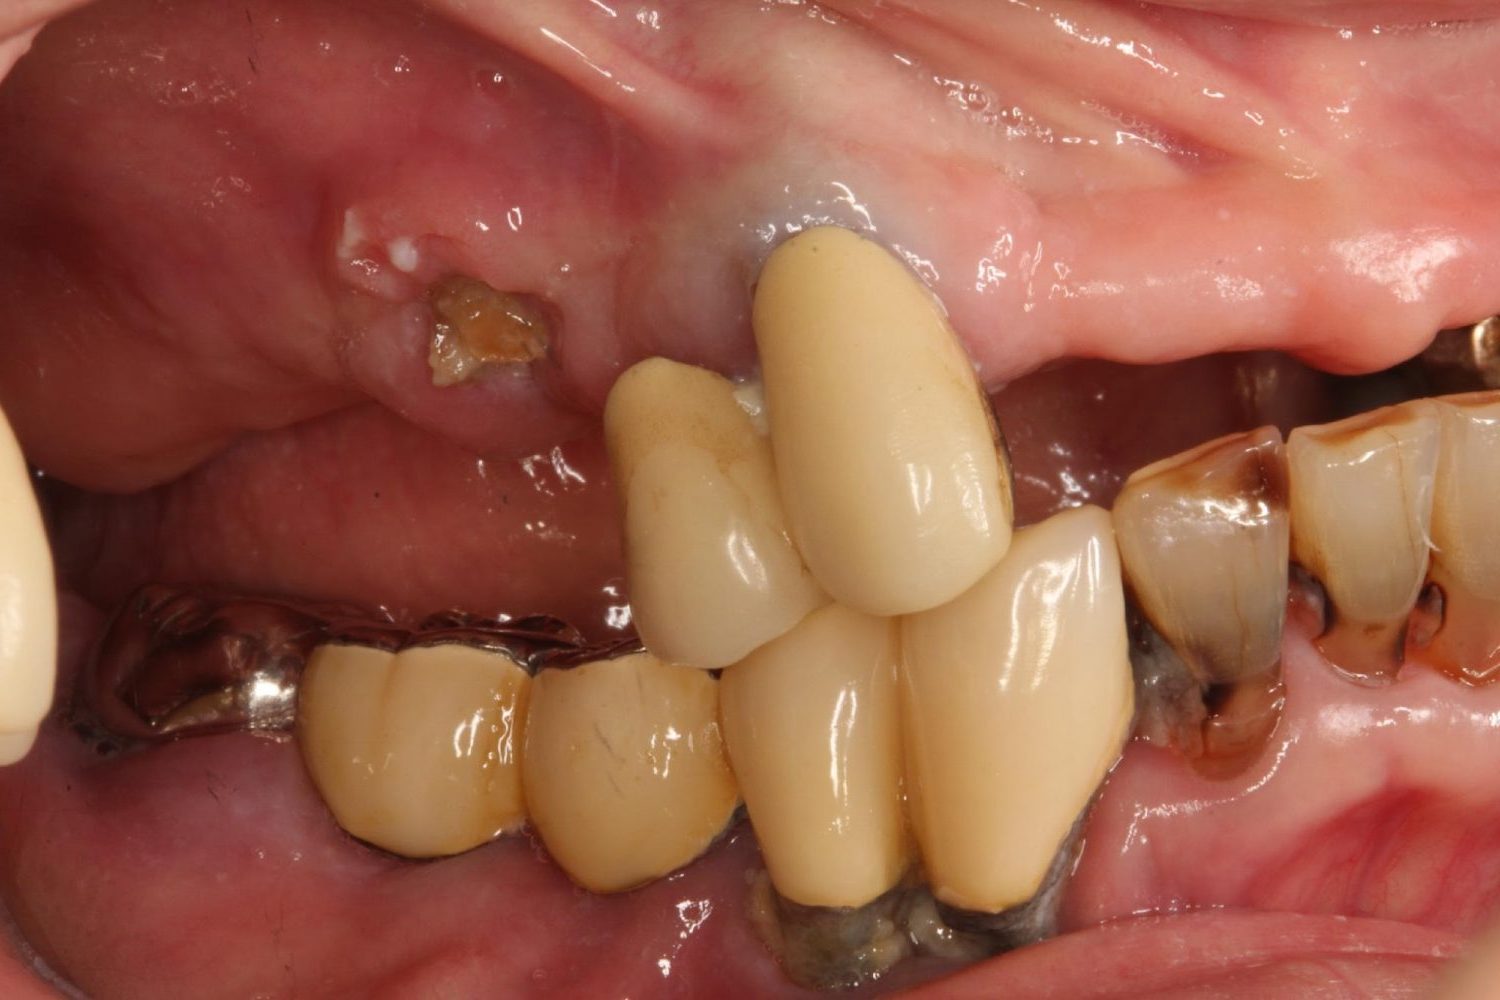

インプラント治療の症例紹介④

Before

After

主訴

義歯による疼痛

治療内容

下顎舌側に骨隆起があり義歯困難な状態。保存不可能な歯の抜歯を行い、インプラントを埋入し咬合再構成を行った。

治療費

2,851,200円(税込)

治療期間

29ヶ月

通院回数

26回

想定されたリスク

※咬合力の強い方なので、予防的にマウスピースの装着が必要。インプラント周囲炎の恐れがありました。

歯の欠損の対合歯の挺出等を修正し咬合平面を揃え咬合再構成を行った症例。